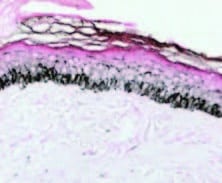

Epidermal melanin density in melasma before procedure

Reduction in epidermal melanin density 1 week after microneedling procedure

Cassiano et al., Indian Journal of Dermatology, Venereology and Leprology | Volume 85 | Issue 6 | November-December 2019